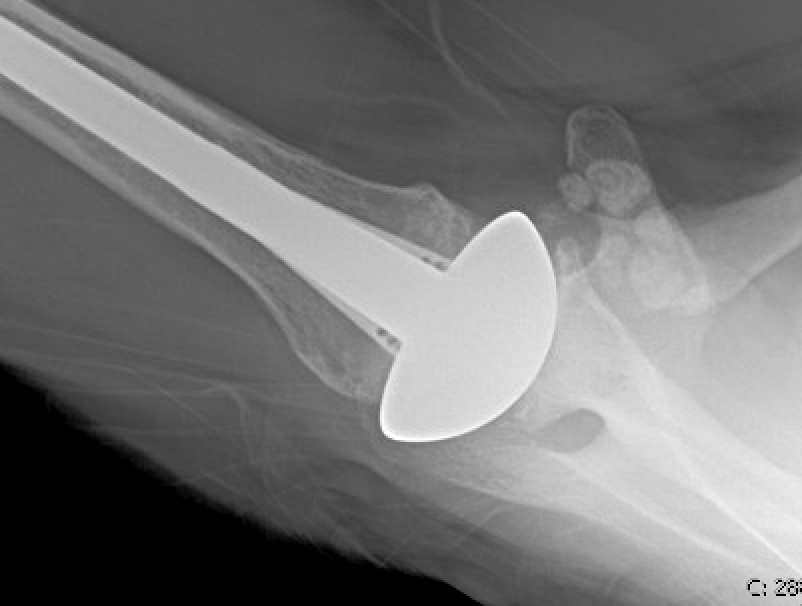

Comment: The presentation of RnR and aTSA outcomes in this review indicates that each of the two procedures can yield excellent clinical outcomes for appropriately selected patients. The aTSA remains the preferred procedure for most patients having osteoarthritis with an intact rotator cuff, especially for women and for those who do not wish to participate in heavy or impact activities.

The RnR remains a consideration for young, active male patients

who wish to avoid the risks and limitations associated with a polyethylene glenoid component.